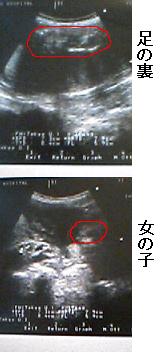

女の子 胎児 小さめ

女の子 胎児 小さめ-うちの子、大きい?小さい? 胎児発育曲線q&a 超音波検査で、医師から「大きいね」「小さめかな?」なんて言われると、なんだか気になる、おなかの赤ちゃん、ちゃんと育っているのかな? 「胎児の大きさ」って、何が正常で、どうなると異常な3 胎児の週数ごとの体重の平均値は? 31 胎児の体重を判断するときに使われる「標準偏差sd」とは?;